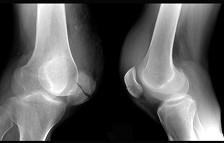

引起图示横形骨折的病因多为 ( )A、病理性骨折B、直接暴力C、间接暴力D、积累性劳损E、肌肉的猛烈收缩

问题 引起图示横形骨折的病因多为 ( )

选项 A、病理性骨折 B、直接暴力 C、间接暴力 D、积累性劳损 E、肌肉的猛烈收缩

答案 E